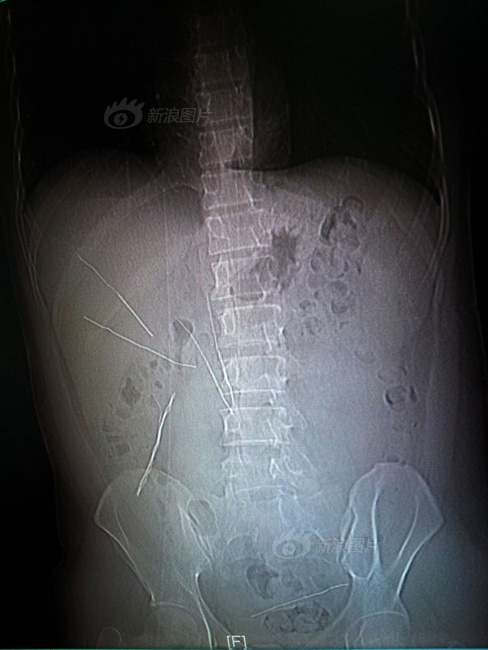

Trong cơn tức giận vì cãi nhau với vợ, một thanh niên Trung Quốc đã nuốt vài đoạn dây thép, nhưng anh không chết nhờ sự can thiệp của bác sĩ.